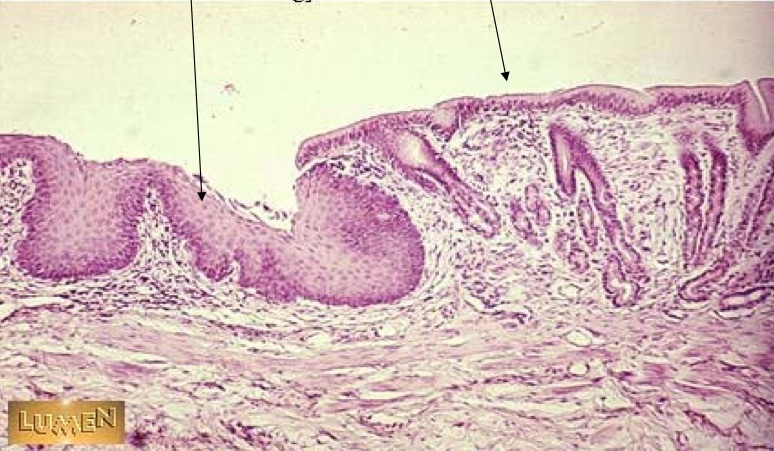

What type of cells are found in the mouth?

Stratified Squamous epithealium

Name the type of cells found in the Pharynx and Esophagus.

Stratified squamous epithelium